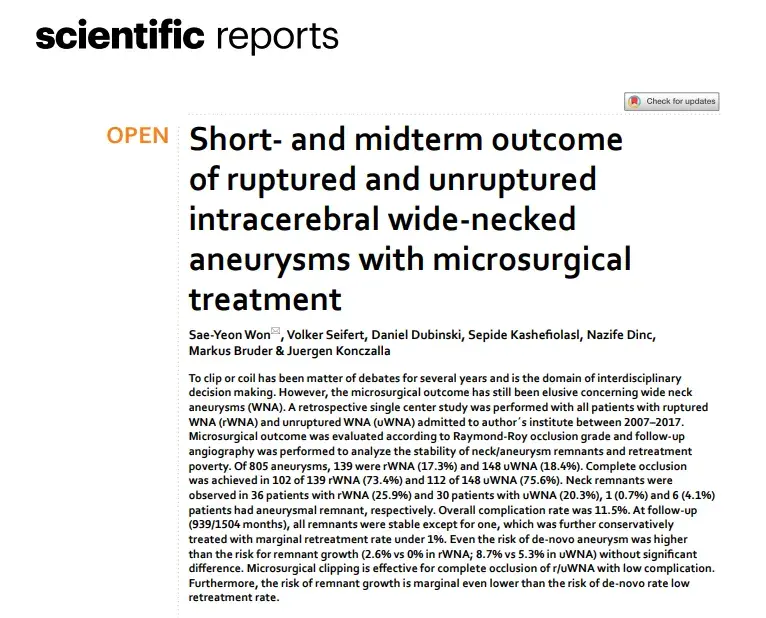

夹闭还是栓塞多年来一直是争论的话题,并且是跨学科决策的领域。然而,关于宽颈动脉瘤(WNA)的显微手术结果仍然难以确定。INC国际神经外科医生集团旗下组织世界神经外科顾问团(WANG)成员...

小男孩多多在3岁时曾用小夹子封印了脑袋里的动脉瘤炸弹,就在全家以为通关成功时,结果6岁复查发现动脉瘤复发,竟还偷偷膨胀成梭形大瘤! 颅内动脉瘤无论是开颅夹闭还是介入栓塞,术后...

眼皮突然耷拉下来,看东西重影?很多人第一反应是去挂眼科,但问题可能出在大脑里。 第三神经受压导致动眼神经麻痹(ONP)是后交通动脉(PcomA)动脉瘤患者的常见首发症状,在某些情况下...